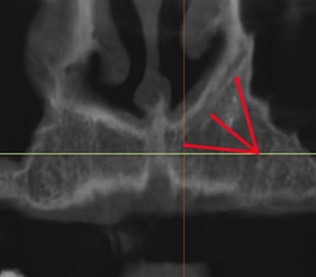

Canalis sinuosus (CS) — это внутрикостная структура, по которой проходит передний верхний альвеолярный нервно-сосудистый пучок¹. Он начинается в подглазничном канале позади одноимённого отверстия и направляется в передне-латеральную сторону. Достигнув передней стенки верхней челюсти, канал поворачивает медиально и проходит вдоль латеральной стенки полости носа⁵. Ряд авторов по-разному обозначают терминальную часть CS, расположенную в альвеолярном отростке верхней челюсти: как «продолжение CS»¹,⁶,⁷, как «добавочный канал CS»⁵,⁸ или как «латеральный резцовый канал»⁹ (Рис. 1).

Рисунок 1. Панорамный вид КЛКТ, КС визуализируется в боковой стенке полости носа, проходя через альвеолярный гребень верхней челюсти.